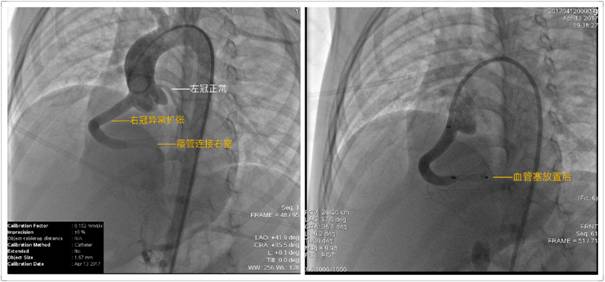

此次新开展的冠脉瘘介入治疗,正是心内科在千余台介入手术基础上的全新探索,纯熟的技术、丰富的手术经验是开展介入新病种的基础。这次的右冠侧枝瘘管封堵手术,极大费尽心思和体力。心脏冠脉侧枝丰富,导丝极易进入非预定冠脉;通过影像科术前术中的精准测量,可见直径约2mm,长度约12mm细小狭长的瘘管,瘘管远端连接右心室,而开口处靠近三尖瓣,意味着血管塞固定过程中稍有不慎便会伤及瓣膜,于是全程谨小慎微,胆大心细,在精确定位后,一步到位、封堵成功。

冠状动脉瘘是一种罕见的心血管发育畸形,人群患病率万分之二,在所有心血管检查患者中,阳性率也仅占0.1%-0.2%,本病可为呼吸困难、反复感染、心肌梗塞的原因,漏诊率高,且远期预后差。该患儿进行PDA随访时,彩超检查发现冠脉发育异常,可见右侧冠状动脉侧枝畸形,最宽处达5.6mm,畸形血管远端经瘘管汇入右心室(术中造影影像)。虽目前无特殊症状,但如不治疗,将逐渐出现心肌缺血、心肌梗死、心脏衰竭等病症。